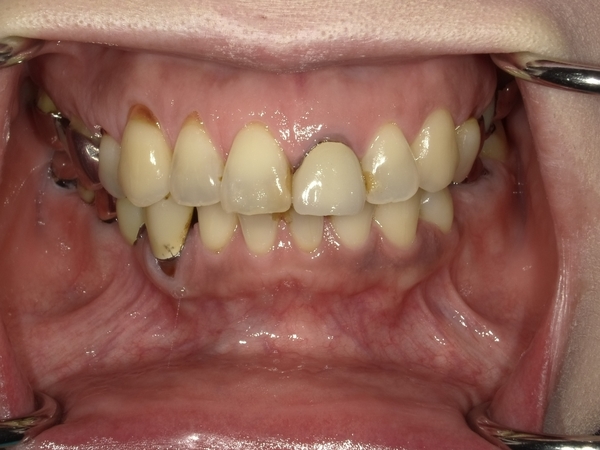

〇ご相談内容:歯並びがよくない〇矯正の種類:マウスピース型矯正「インビザライン」〇治療期間:39週間〇治療費用:44万円(税込)